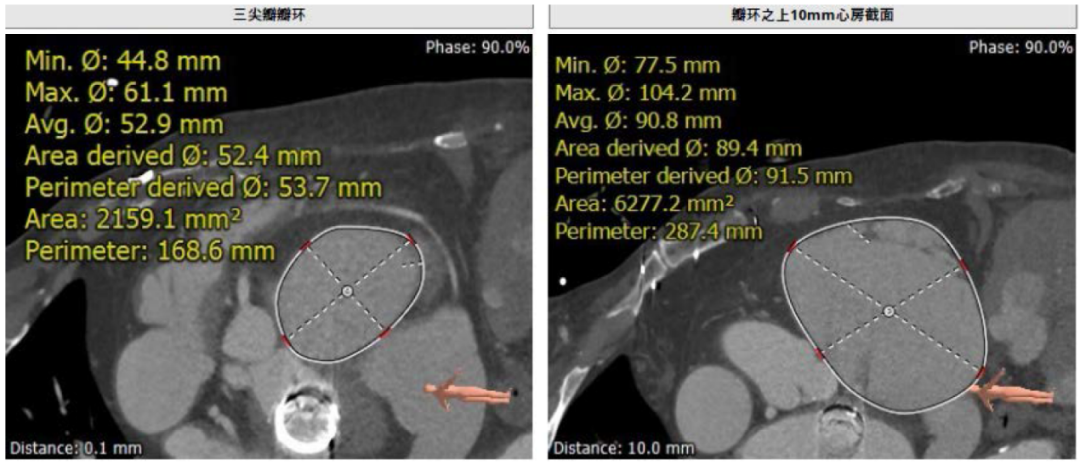

接受治疗的是三例重度三尖瓣反流患者,术前基础疾病多,均患有严重心律失常,其中两例患者NYHA心功能Ⅱ/Ⅲ级。结合术前CT评估结果,三例患者的自体瓣环都较大(图1-3),最大者平均瓣环为53.7mm;有一例患者有起搏器植入史,术中操作有缠绕起搏器导线的风险;三例患者入路血管均无严重迂曲和钙化。经术前讨论分析,潘湘斌教授及其团队潘家华教授、朱达教授、王首正教授以及心超室的骆志玲教授,董念国教授及其团队谢明星教授、尚小珂教授、陈澍教授、钟禹成教授经过讨论决定,采用创新的 LuX-Valve Plus经血管三尖瓣置换系统对患者进行手术。LuX-Valve Plus是我国自主研发的经血管介入三尖瓣置换系统,经颈静脉入路的微创方式可进一步降低对患者的创伤。

图1-3. 术前CT评估三例患者瓣环大小